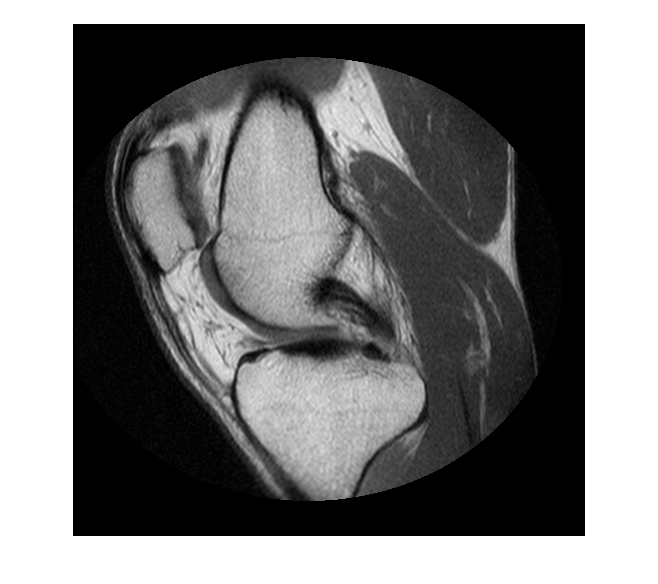

Считайте данные MRI в рабочую область.

im = dicomread('knee1.dcm');

Отобразите изображение.

figure hImage = imshow(im, []);